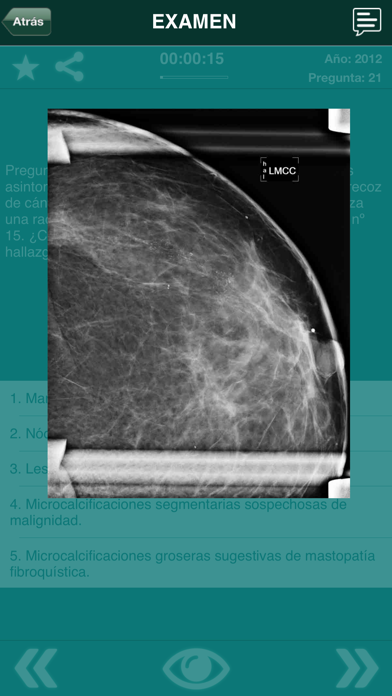

Incluye todas las preguntas y respuestas de los exámenes oficiales del examen de acceso a Médico Interno Residente desde el año 2001 a 2018 con todas las imágenes.